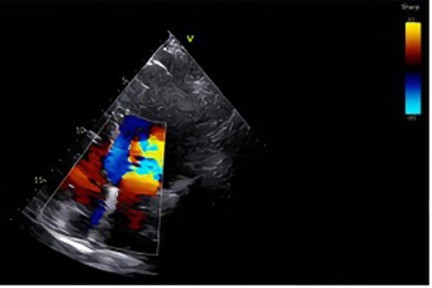

A 24-year-old woman was admitted at 27 + 6 weeks of gestation due to recurrent hemoptysis. She reported a sudden onset of coughing during sleep without any identifiable trigger, followed by expectoration of approximately 20 ml of bright red blood. The episode was accompanied by orthopnea, but there were no symptoms of chest pain, dyspnea, or fever. The patient had no significant past medical history, including no hypertension, coronary artery disease, diabetes mellitus, hyperthyroidism, or exposure to toxins or radiation. On admission, physical examination revealed bilateral lower limb edema. Her vital signs were: temperature 37.4 ℃, heart rate 126 bpm, respiratory rate 20 /min, blood pressure 120/70 mmHg, and oxygen saturation 93% under oxygen therapy (Oxygen inhalation state). Transthoracic echocardiography with contrast revealed a positive right heart contrast study, suggesting the presence of a PAVM (Figure 1). Subsequent contrast-enhanced pulmonary artery CT further confirmed the diagnosis, indicating a pulmonary arteriovenous malformation in the upper lobe of the left lung, suggesting by localized pulmonary atelectasis (Figure 2). A multidisciplinary consultation was conducted. Based on the patient's history, physical findings, and auxiliary tests, the final diagnoses were: pregnancy complicated with pulmonary hemorrhage, pulmonary arteriovenous fistula, pulmonary infection, congenital pulmonary vascular malformation, pregnancy with hypothyroidism, type I respiratory failure, pregnancy with sinus tachycardia, hypokalemia, and respiratory alkalosis.

Figure 1. In the lower left to mid region of the image, a distinct mosaic flow signal comprising red, blue, and yellow is observed, located near the posterior wall of the atrium or the pulmonary vein inflow area. Under physiological conditions, color Doppler signals are typically confined to the valvular orifice and adjacent flow regions. However, in this case, the jet deviates from the valvular axis and traverses obliquely upward, suggesting the presence of an abnormal flow pathway from a non-physiological direction. This imaging feature raises suspicion of a pulmonary arteriovenous malformation (PAVM), which may facilitate a right-to-left shunt.